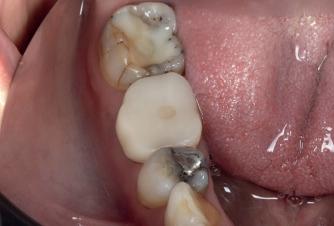

Case 1: Anterior tooth restoration with composite

Case 2: Posterior tooth restoration with composite

Restorations with Beautifil II LS, Beautifil Flow Plus X and OneGloss by Erik-Jan Muts, M.Sc., Netherlands